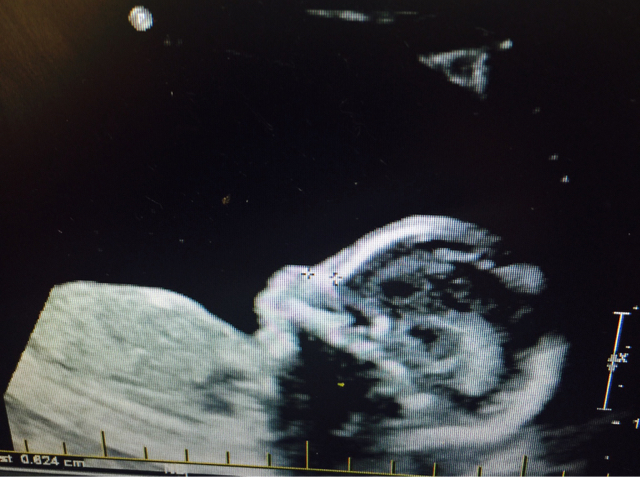

Please any guesses ? Scull theory?